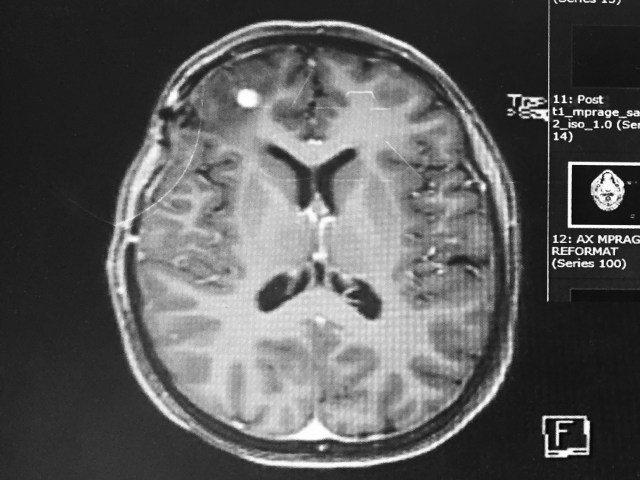

I love this quote. It’s totally true. But sometimes it’s a tumor or two tumors and not a brick. Either way, they both hurt. I’ll get right to the Promiscuity part because clearly I don’t want to give anyone the wrong idea. Now, we already know that Hannibal and Clarice had a baby in my brain this summer. What we now know is that there were more babies. Babies that are now growing up into toddlers.

I have two more brain tumors. As my best friend said, “Clarice and Hannibal were having a lot of sex up there and now you have to take care of all their kids.” We use humor so much when processing my illness. It makes everything easier to deal with. It’s not denial, it’s not, not taking this seriously. Trust me, I’m taking this very seriously. As I sit here, tears are falling down my face and my sweatshirt and I’m wiping my eyes so I can keep writing. This is very real.

I try very hard not to lose faith, ever again. It’s hard somedays when all I feel is defeat. Sometimes it’s too much work trying to hold onto hope and faith so tightly. So, the two tumors have both doubled in size in the last 60 days. I’ll have another gamma knife surgery in the next 10 days. I’ve also decided to stop naming my tumors, they’re now receiving numbers. These are tumor 4 and tumor 5.

I’m now almost 10 months out from going from remission to incurable. The stats say 10-14 months but I’m not following those rules, thankfully. Yes, I may be getting new brain tumors every two months thus far but they’re “manageable”, right now. Yesterday, as I asked one of my oncologists through a few tears, about my prognosis, he assured me that we are still in a completely good place. I asked him if he would tell me when he thought the shit was hitting the fan so to speak. He said absolutely.

My other neuro oncologist said, if more grow after this treatment then she would like to see me in an immunotherapy clinical trial. At least there’s that option as well. I’ll never be ‘curable’. I know never say never but the realist in me knows better. BUT, I may have a lot more time then 10-14 months. I guess breaking the cancer rules is finally paying off.